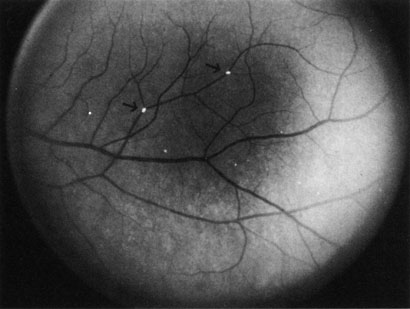

CAROTID ARTERY DISEASE The principal cause of chronic arterial obstruction is usually some kind of carotid artery disease. Atherosclerosis is the most common cause of carotid artery disease in the United States but there are other causes, such as moyamoya disease,148 fibromuscular dysplasia,149 and irradiation.150 Atherosclerosis is a disease affecting medium-sized arteries in humans. The primary symptoms of carotid artery disease are caused by the atheromatous or fibromuscular plaque.151,152 Atherosclerosis may result in narrowing (obstruction) or occlusion of the artery or in embolization. The bifurcation of the common carotid artery into the external and internal carotid artery is one of the sites at particular risk for atheromatous disease.153 The eye is frequently involved in atheromatous disease of the carotid artery bifurcation because the ophthalmic artery is one of the first branches of the internal carotid artery in the neck. Carotid artery disease can be manifest by a variety of ocular and non ocular symptoms. The ocular manifestations are important—not only because they occur in many patients with carotid insufficiency154 but also because they often are the first indication that carotid artery disease exists. There are many ways that patients with carotid artery disease present to the ophthalmologist.8 Some present with a TIA. If the TIA involves the carotid system, the symptoms include hemiparesis, hemisensory loss, aphasia, and transient monocular blindness (amaurosis fugax).155 Another group of patients have symptoms that are purely ocular. These patients present with one of several symptoms, such as (i) partial or complete visual loss due to an artery obstruction, (ii) decreased visual acuity, or (iii) pain resulting from the ocular ischemic syndrome. Other patients are asymptomatic and any ocular findings consistent with carotid artery disease are incidental. Amaurosis Fugax The type of TIA known as amaurosis fugax is the most common symptom of carotid artery disease.154,156 Amaurosis fugax is characterized by a sudden, painless, monocular loss of vision that typically lasts between 2 and 10 minutes. The patient frequently describes his or her vision as being “dark” or “dim.” The return of vision can be sectorial or altitudinal and is occasionally described as a “curtain rising.” Generally, the vision returns to normal immediately after an attack. The frequency of these attacks varies from 1 or 2 attacks per month to 10 or 20 per day. The retina—if observed during an amaurotic attack—may be normal155 or it may show obstruction (such as in central retinal artery obstruction). It may exhibit migratory white retinal emboli (within the retinal arterioles and in association with disruption of the arterial circulation)157 or it may show cholesterol emboli moving through the arterial system.155 It is important to recognize amaurosis fugax as a TIA because it is frequently caused by microembolization from an atheromatous ulcerative lesion in the ipsilateral extracranial carotid artery, at least in older patients.158,159 Approximately one-third of all patients with an untreated TIA can be expected to have a stroke; this rate is about four times greater than that of an age-matched population.160 It must be noted, however, that not all amaurosis fugax and other forms of TIA are caused by carotid artery disease. Other causes of amaurosis fugax include temporal arteritis,161 pseudotumor cerebri,161 migraine,161 structural cardiac defects,162 ophthalmic artery stenosis,163 ophthalmic artery aneurysms, hematology disorders,164,165 ocular hypertension,160 arterial hypotension, and vasospasm.165 A group—usually younger patients—may have no identifiable disease.161,162,167 Ocular Ischemia There are several forms of chronic arterial obstructions that occur in carotid artery disease. These typically result from hypoperfusion of the retina caused by either stenosis or the complete obstruction of either the extracranial internal or the common carotid artery. One form of chronic arterial occlusion is a unilateral retinopathy that is ipsilateral to the carotid artery lesion and is characterized by cotton-wool patches, dilated arterioles and veins, an absence of hemorrhages, and normal vision. This retinopathy was first recognized as a sign of carotid artery disease by Hollenhorst154 in 1958, although such changes had been previously noted after ligation of the common and external carotid arteries in the treatment of traumatic carotid cavernous fistula.168 In a milder form of this retinopathy, the only abnormality may be larger retinal arterioles on the side of a ligated carotid artery in patients with hypertension169 or asymmetric hypertensive retinal vascular changes, in which the eye ipsilateral to the carotid lesion has the fewer changes.8 Another type of chronic ophthalmic artery obstruction produced by hypoperfusion caused by stenosis or occlusion of the ipsilateral extracranial carotid artery was first reported by Hedges170 and termed venous stasis retinopathy by Kearns and Hollenhorst.171 Venous stasis retinopathy is probably not a good term for this condition, however, because the basic mechanism involves reduction of the arterial inflow, not the venous outflow. Even more confusion has resulted from the use of the term to describe the features of the nonischemic form of central retinal vein obstruction.172 A better term is hypoperfusion or hypotensive retinopathy.172 Klijin and co-workers414 found this type of chronic ocular ischemia in approximately one-third of patients studied with symptomatic carotid artery occlusive disease. Hypoperfusion retinopathy is characterized by dot and blot hemorrhages in the midperiphery of the fundus, by venous tortuosity and engorgement, by microaneurysms, and by the occasional sludging of blood within the veins. Fluorescein angiography may show areas of capillary nonperfusion; it may also show microaneurysms in the midperiphery and slow arm to retina or arteriovenous transit time (Fig. 9A and 9B).174 The condition does not usually affect the posterior pole, and patients typically have normal visual acuity, although an occasional patient may have macular edema.174 The entire periphery of the eye is usually affected, although there may be more hemorrhages in one quadrant than another. Patients occasionally experience ocular discomfort or eye pain despite normal intraocular pressure. Reduction of the ophthalmic arterial pressure is a pathognomonic feature. Disc edema and disc collaterals are generally not present. The electroretinogram shows abnormalities in both the a- and b-waves (see Fig. 9C).